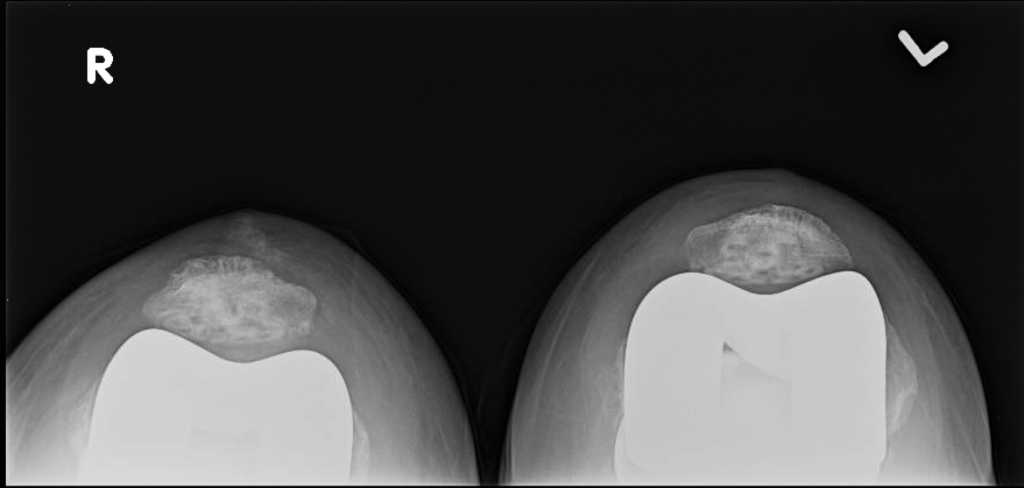

This is a 66 year old female with severe, end stage arthritis of bilateral knees. She delayed surgery for over a decade due to fear of the procedure. Subsequently, she developed significant loss of motion due to the formation of extremely large osteophytes (bone spurs). Her preoperative range of motion was only 15 to 90 degrees.

She underwent staged bilateral total knee arthroplasty, spaced two months apart, without issues.